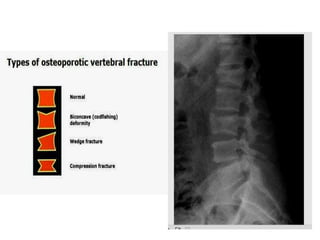

Types

• Primary and Secondary types

• Type I primary osteoporosis has been called

postmenopausal osteoporosis because it affects many

more women than men associated with the dramatic loss

of estrogen. Active trabecular bone is lost. Vertebral

fractures are more common.

• Type II primary osteoporosis is associated with ages 70

years in both sexes and affects both trabecular and

cortical bone. Therefore both vertebral and hip fractures

occur in such patients.

• Vertebral fracture is the most common clinical

manifestation of osteoporosis

• The pain from a vertebral compression fracture is

variable in quality and may be sharp or dull aggravated

by sitting, spine extension, Valsalva maneuver, and

movement and mostly assosiated with sleep disturbance.

• kyphosis ("dowager hump") may be an indicator of

multiple vertebral compression fractures.